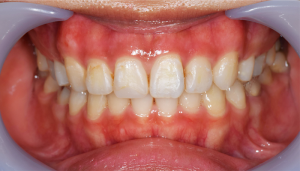

歯石除去

治療前

治療後

| 年齢 | 40歳・男性 |

|---|---|

| 主訴 | 歯石をとりたい |

| 治療内容 | 歯石除去 |

| 治療期間 | 30分 |

| 費用 | 約2,000円 |

| リスク・副作用 | ・歯ぐきの炎症が強いと歯石を取る際に出血することがあります。 ・処置後に歯がしみることがあります。 ・歯と歯の間に隙間ができるので、息が漏れ発音しにくいと感じることがあります。 ・歯ぐきの炎症が軽減すると歯ぐきが引き締まり、歯が長く見えることがあります。 |